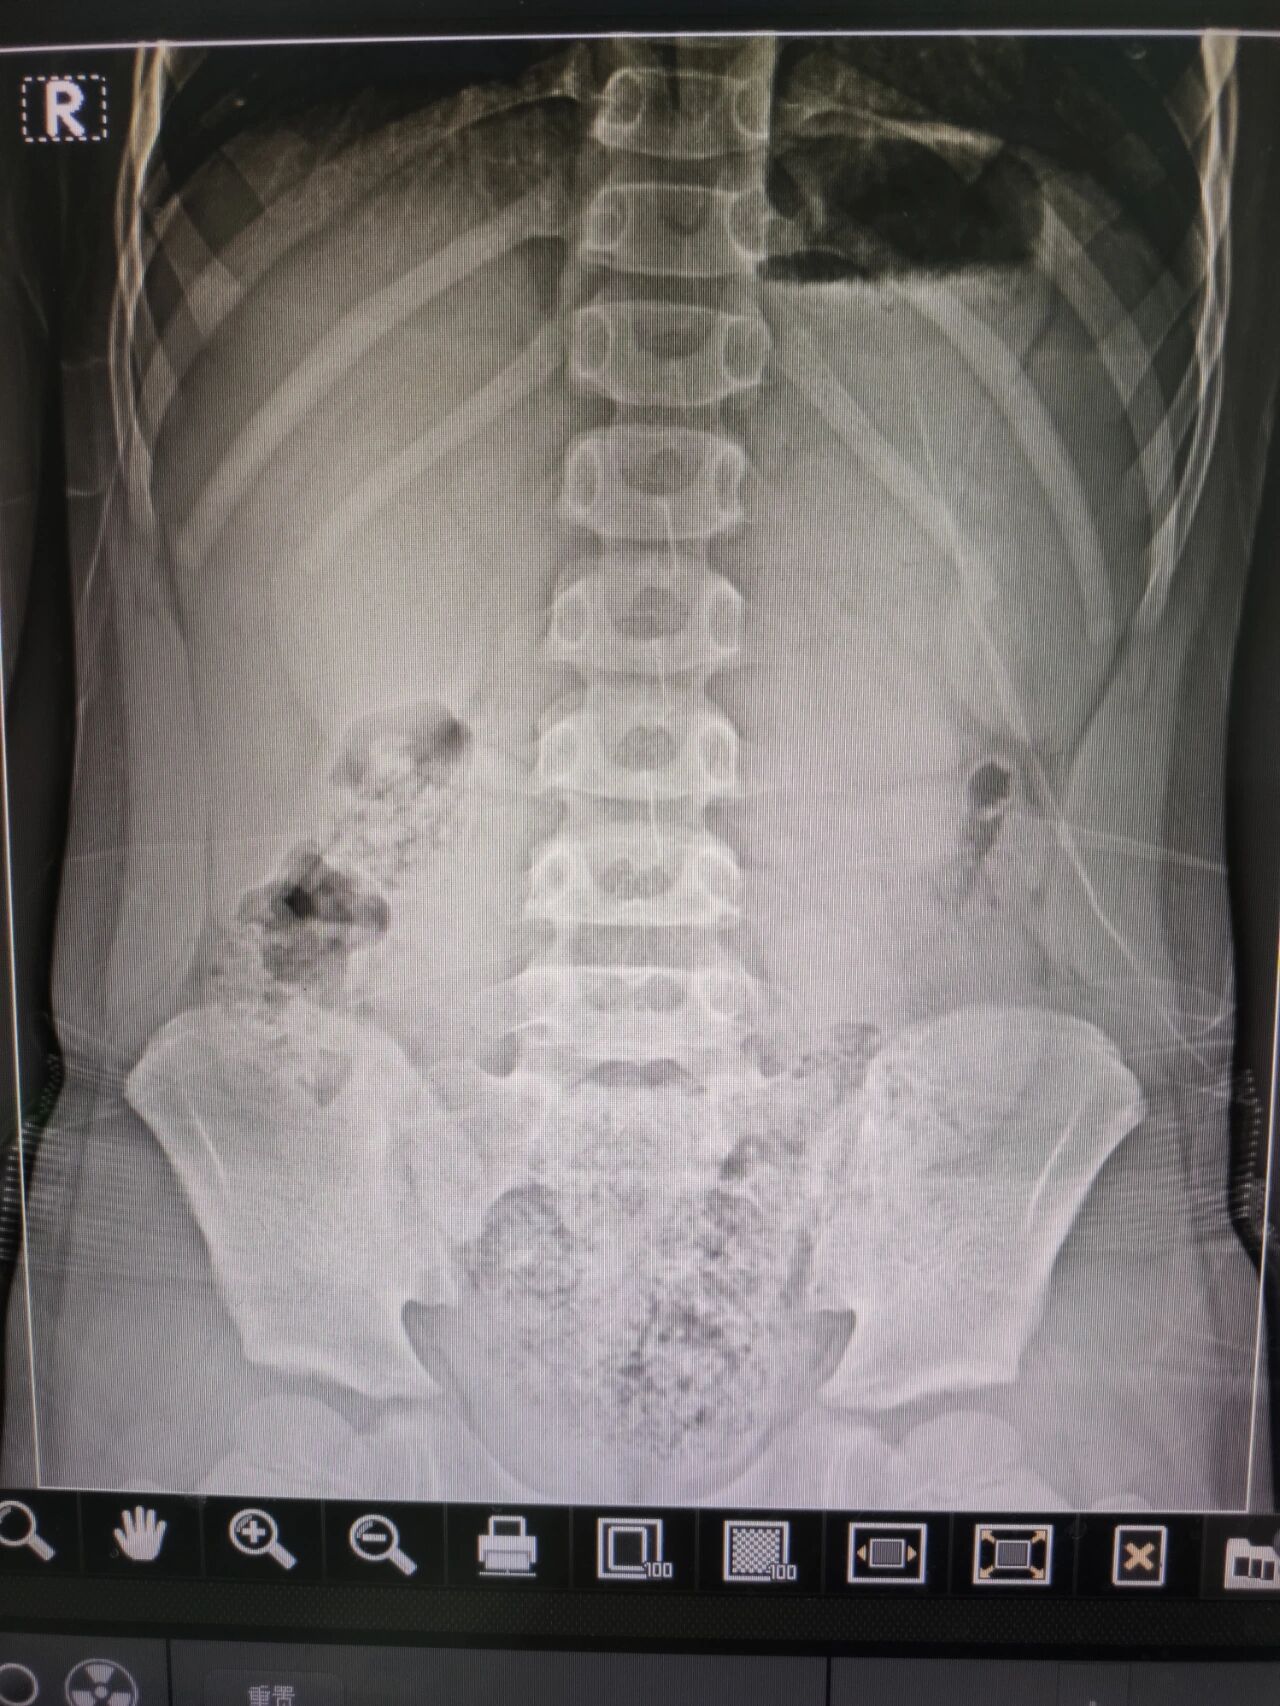

请帮我看看立位腹部平片是啥问题

图片尺寸768x1024